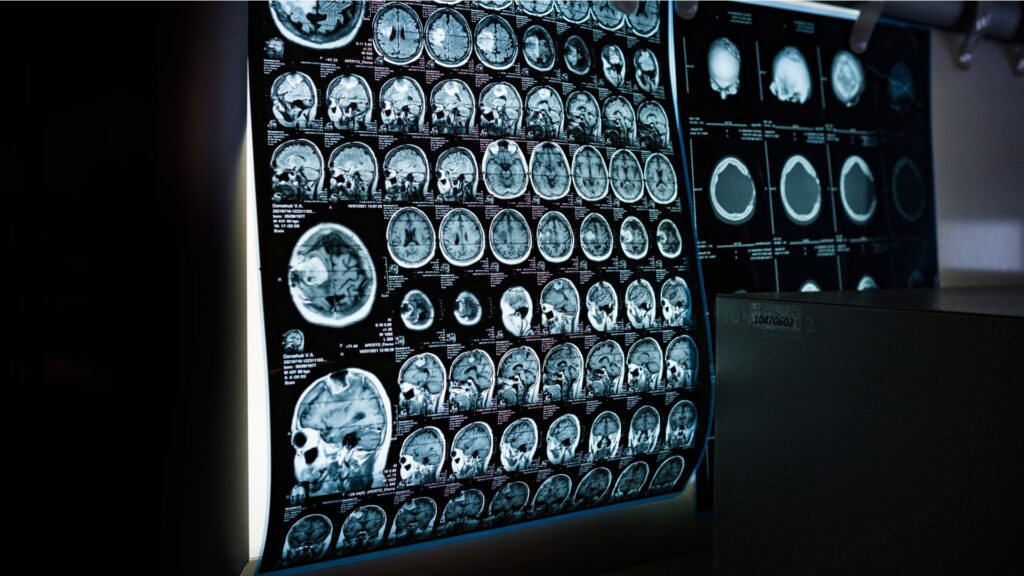

Pemikiran ini muncul karena disleksia sering disebut sebagai gangguan neurodevelopmental. Kata “neuro” kemudian diasosiasikan langsung dengan pemeriksaan radiologi atau rekam otak. Namun demikian, asumsi tersebut kurang tepat. Faktanya, disleksia tidak didiagnosis dengan CT Scan atau MRI

Artinya, diagnosis disleksia ditegakkan melalui penilaian fungsional, bukan melalui pencitraan struktur otak. CT Scan dan MRI memang dapat melihat struktur otak. Akan tetapi, disleksia tidak menyebabkan kerusakan struktur otak yang terlihat secara kasat mata melalui pemeriksaan tersebut. Oleh karena itu, melakukan CT Scan atau MRI untuk mendiagnosis disleksia tidaklah relevan.

Meskipun tidak diperlukan untuk diagnosis disleksia, pemeriksaan radiologi seperti CT Scan atau MRI dapat dilakukan apabila terdapat indikasi medis lain, misalnya:

Dalam situasi tersebut, pemeriksaan dilakukan untuk mencari kondisi medis lain, bukan untuk menegakkan diagnosis disleksia.